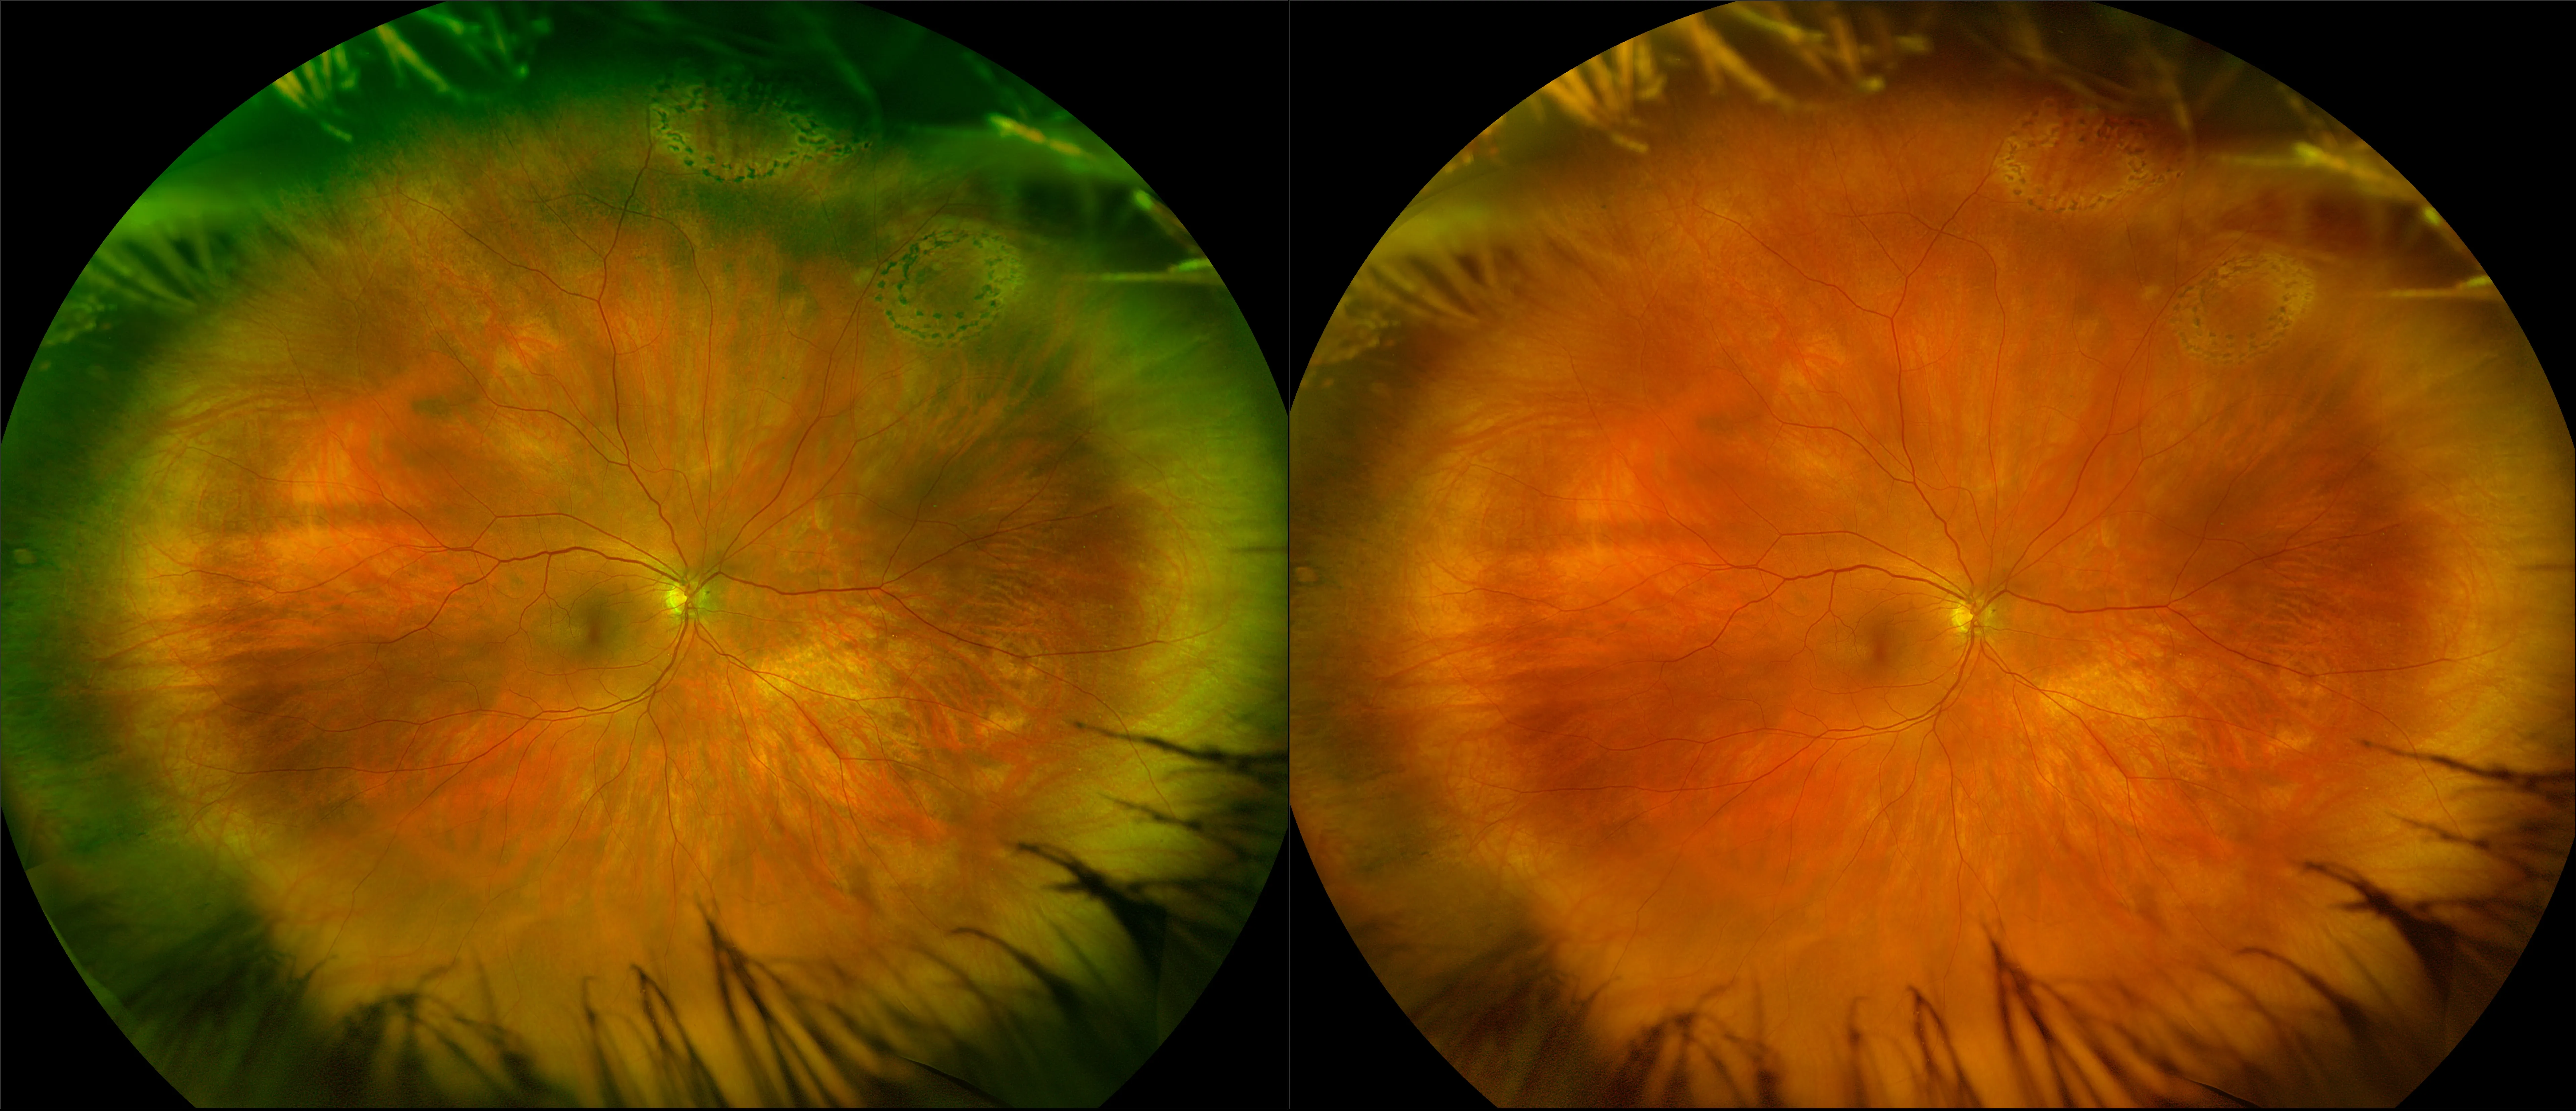

optomap® Recognizing Pathology

This material is designed as a searchable reference resource to support clinical decision-making. The information contained here should be used as general guidance when viewing optomap and OCT images from Optos devices. The differential diagnosis should be made under the direction of the responsible physician. These images were taken on the latest ultra-widefield optomap devices.

The Cases and Images

optomap Recognizing Pathology is searchable by pathology and/or optomap image modality. You may search by multiples of each selection. Each individual case is represented by the accompanying thumbnail image. Most cases include several different optomap image modalities. To view a full description of the case, please click on the thumbnail. Each image in the case will be made available through our OptosAdvance software which provides multi-dimensional visualization of digital images to aid in the analysis of anatomy and pathology. Support and pathology definitions can be found by selecting one of the buttons, above. Should you have questions, please complete the form below.